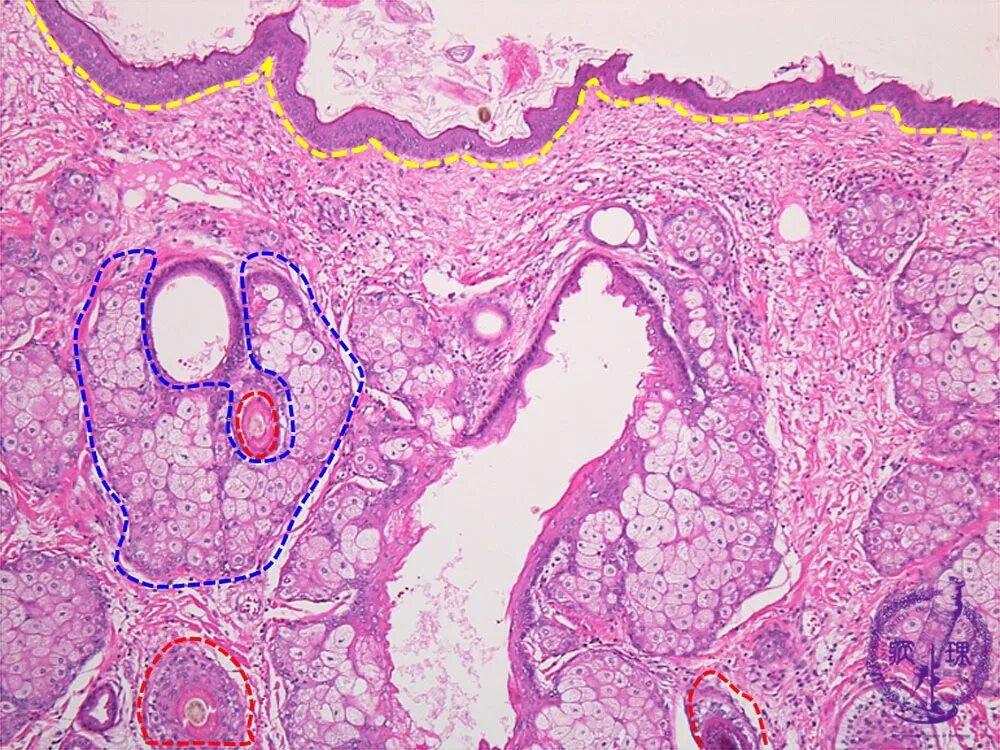

Гистология фото